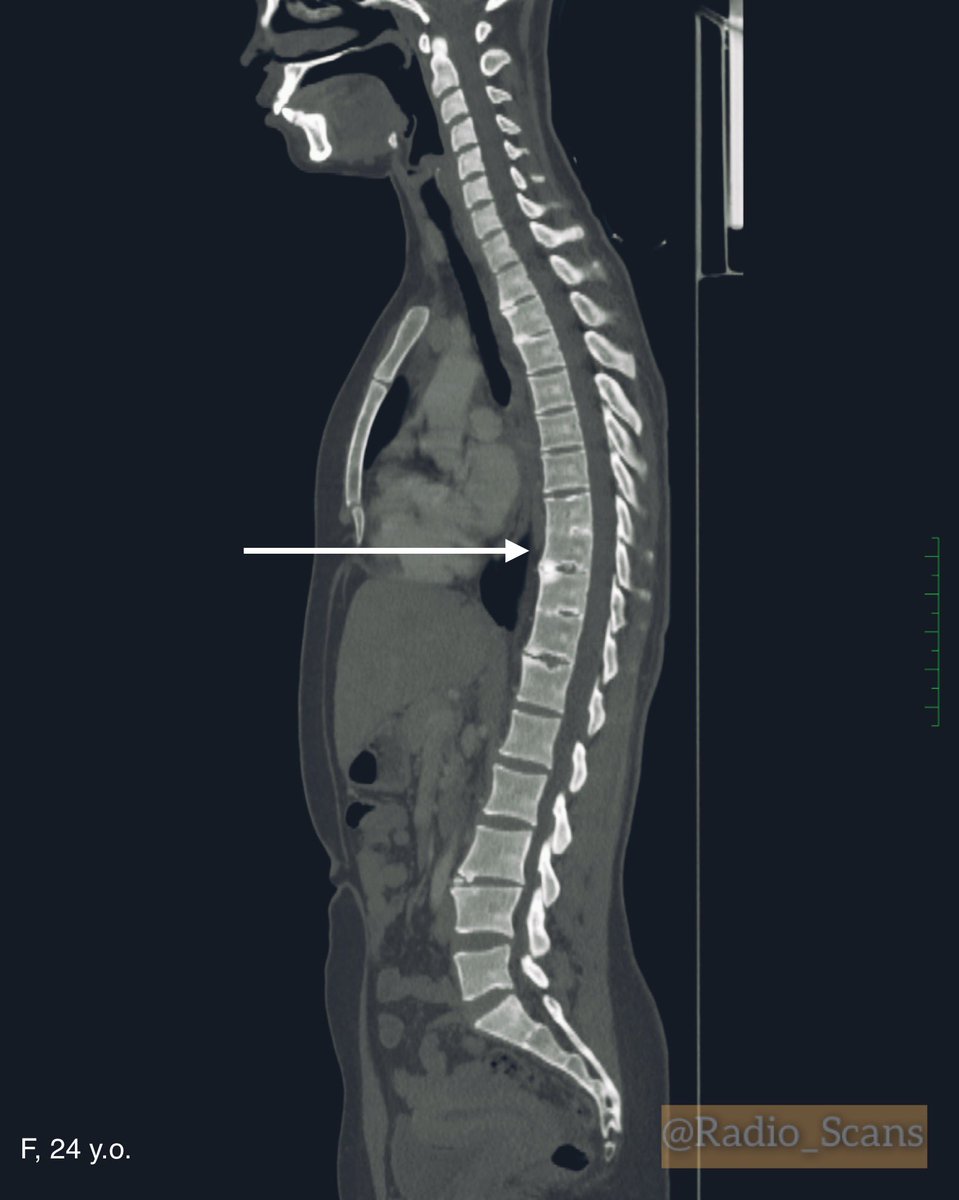

Block vertebrae. CT scans of a 24-year-old female. Notice violation of a failure to separate Th8, Th9, Th10 and Th11 vertebral bodies and blocked vertebrae too. #computed #tomography #ctscan #64slice #blocked #vertebra #failure #separation #vertebral #bodies #anatomic #variant

Radio_Scans's tweet image. Block vertebrae. CT scans of a 24-year-old female. Notice violation of a failure to separate Th8, Th9, Th10 and Th11 vertebral bodies and blocked vertebrae too.